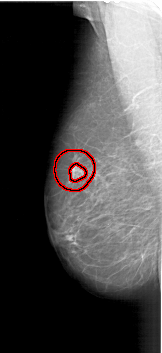

A_1174_1.LEFT_MLO

FILE: A_1174_1.LEFT_MLO.OVERLAY

TOTAL_ABNORMALITIES 1

ABNORMALITY 1

LESION_TYPE MASS SHAPE IRREGULAR MARGINS SPICULATED

ASSESSMENT 5

SUBTLETY 4

PATHOLOGY MALIGNANT

TOTAL_OUTLINES 2

BOUNDARY

CORE